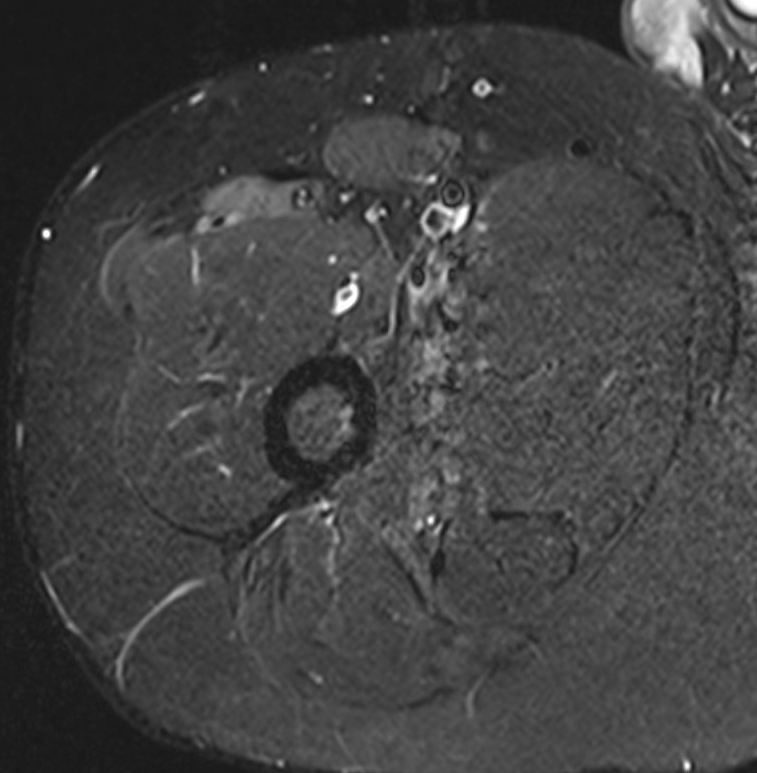

Chronic Grade 4 proximal rectus tear

Grade 4B Rectus femoris musculotendinous injuries